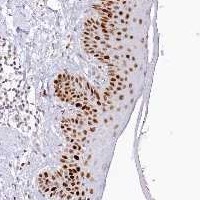

Enhanced - Orthogonal

Antibody staining mainly consistent with RNA expression data across 44 tissues.

HIGH EXPRESSION

Skin 1

RNA expression: 36.4 nTPM

LOW EXPRESSION

Cerebellum

RNA expression: 2.4 nTPM